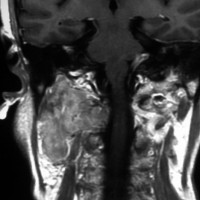

左は1991年,右は2006年のMRI画像です。15年間で腫瘍のサイズは変わっていません。

1991年に50代の女性にみつかったものでした。黄色に示したルートで摘出できないわけではありませんが,右後頭部が腫れてきたという訴えとホルネル症候,軟口蓋麻痺しかなかったので,何も治療しないでほっておきました。2016年まで25年間観察し続けました。症状の悪化は全くなく元気に暮らしておられます。グロームス腫瘍はある一定の年齢になると増大しないという性質を持っている良性腫瘍です。これを大々的な頭蓋底外科手術で摘出するするという愚を犯してはなりません。